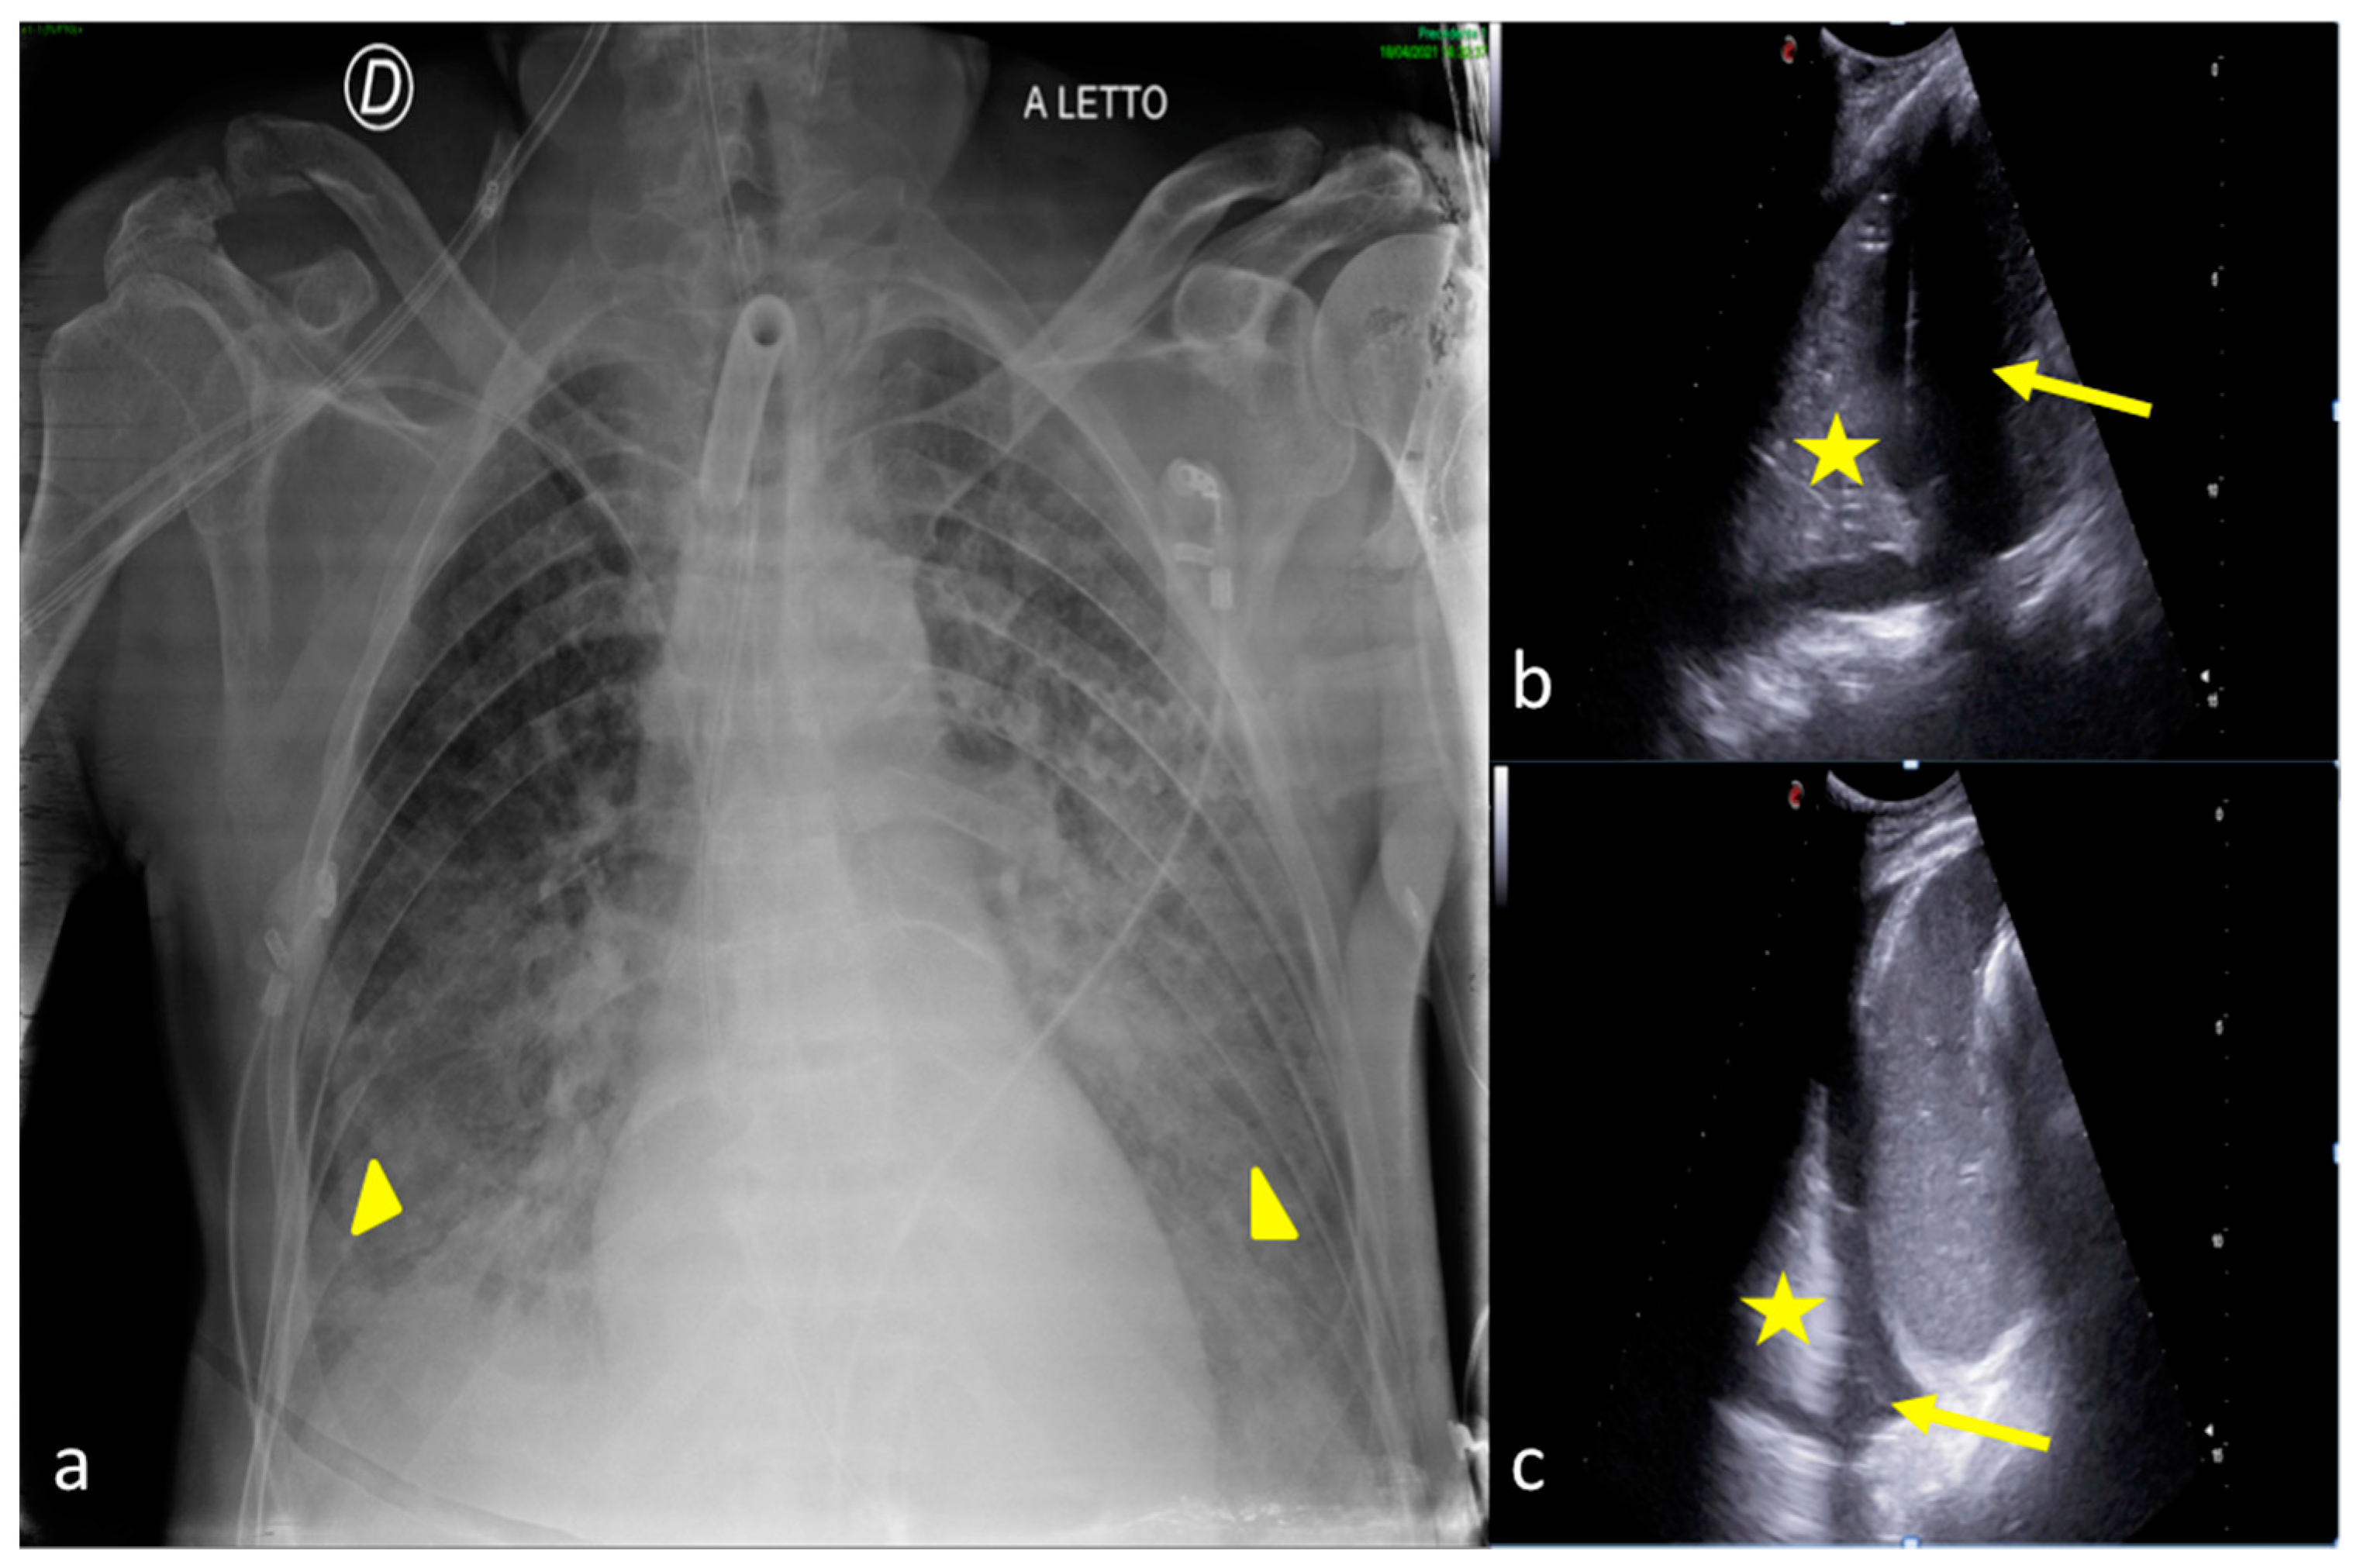

2.4. Cardiogenic Pulmonary Edema

2.5. Acute Respiratory Distress Syndrome